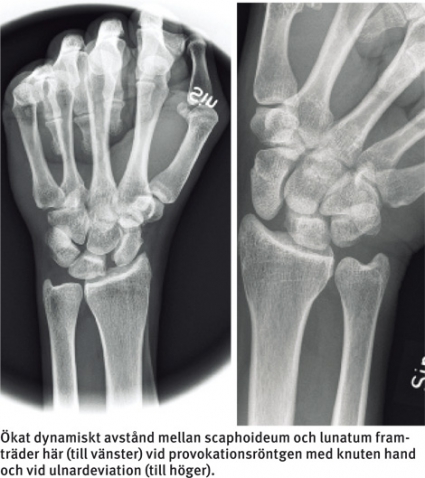

Röntgen med provokationsbilder (knuten hand och deviation) liksom bilder för jämförelse med kontralaterala sidan kan vara ett hjälpmedel – framför allt senare i förloppet! Dessa undersökningar är värdefulla främst vid skafolunära skador, där en dynamisk instabilitet kan utvecklas successivt och där röntgenförändringar framträder tidigast 3–4 månader efter skadan.

Akut tagna röntgenbilder, även med provokation, utesluter alltså inte allvarlig ligamentskada. Alla ligamentskador är initialt dynamiska, dvs framträder enbart vid belastning och provokation. Med tiden blir de statiska. DISI/VISI kan då ses som permanent felställning. DISI innebär radiologiskt indirekt samtidigt att vinkeln mellan scaphoideum och lunatum på sidobilden överstiger 60–80°, jämfört med en normal vinkel på 30–60°. I en sådan situation framträder också en s k skafolunär dissociation. Det skafolunära avståndet på frontalbilden ska normalt sett vara mindre än 3 mm.

Viss interindividuell variation finns, men om avståndet mellan scaphoideum och lunatum överstiger 3 mm ska skada misstänkas (jämför alltid med frisk sida), och mer än 5 mm är alltid patologiskt! Röntgenbilden vid lunotrikvetral skada är oftast helt normal. I undantagsfall kan ett hak mellan lunatum och triquetrum och/eller en överprojektion av lunatum på triquetrum ses. Ibland finner man VISI sent i förloppet. Vanlig röntgen tillför sällan något vid akut diagnostik av TFCC-skador. Vid grav instabilitet ses dock ibland ett ökat avstånd i distala radioulnarleden på frontalbilden och subluxation av caput ulnae på sidobilden.